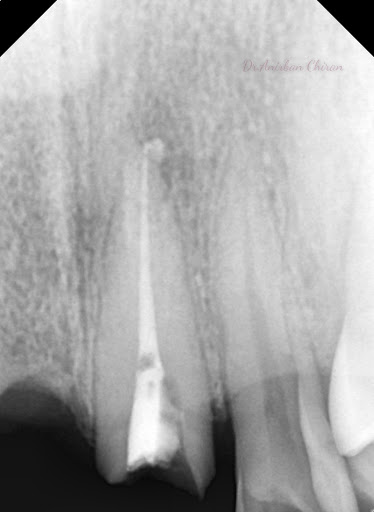

Gallery